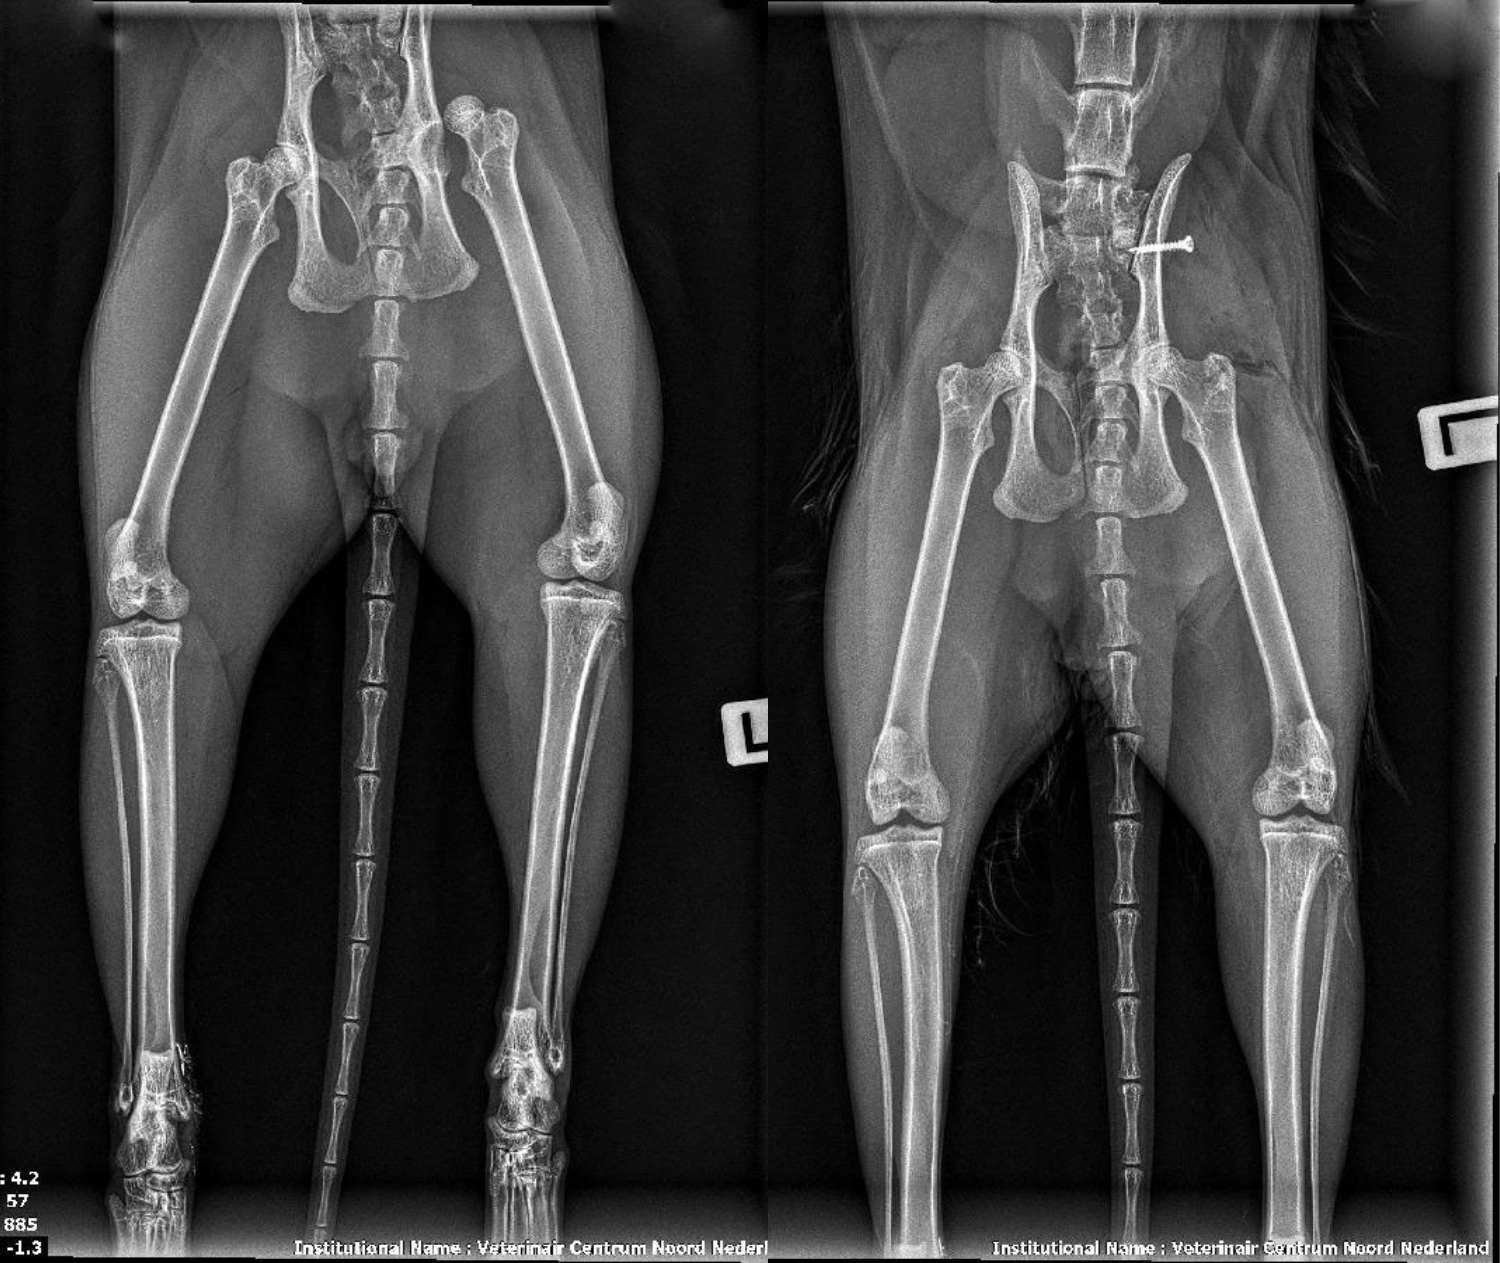

Röntgenfoto vóór en na de operatie